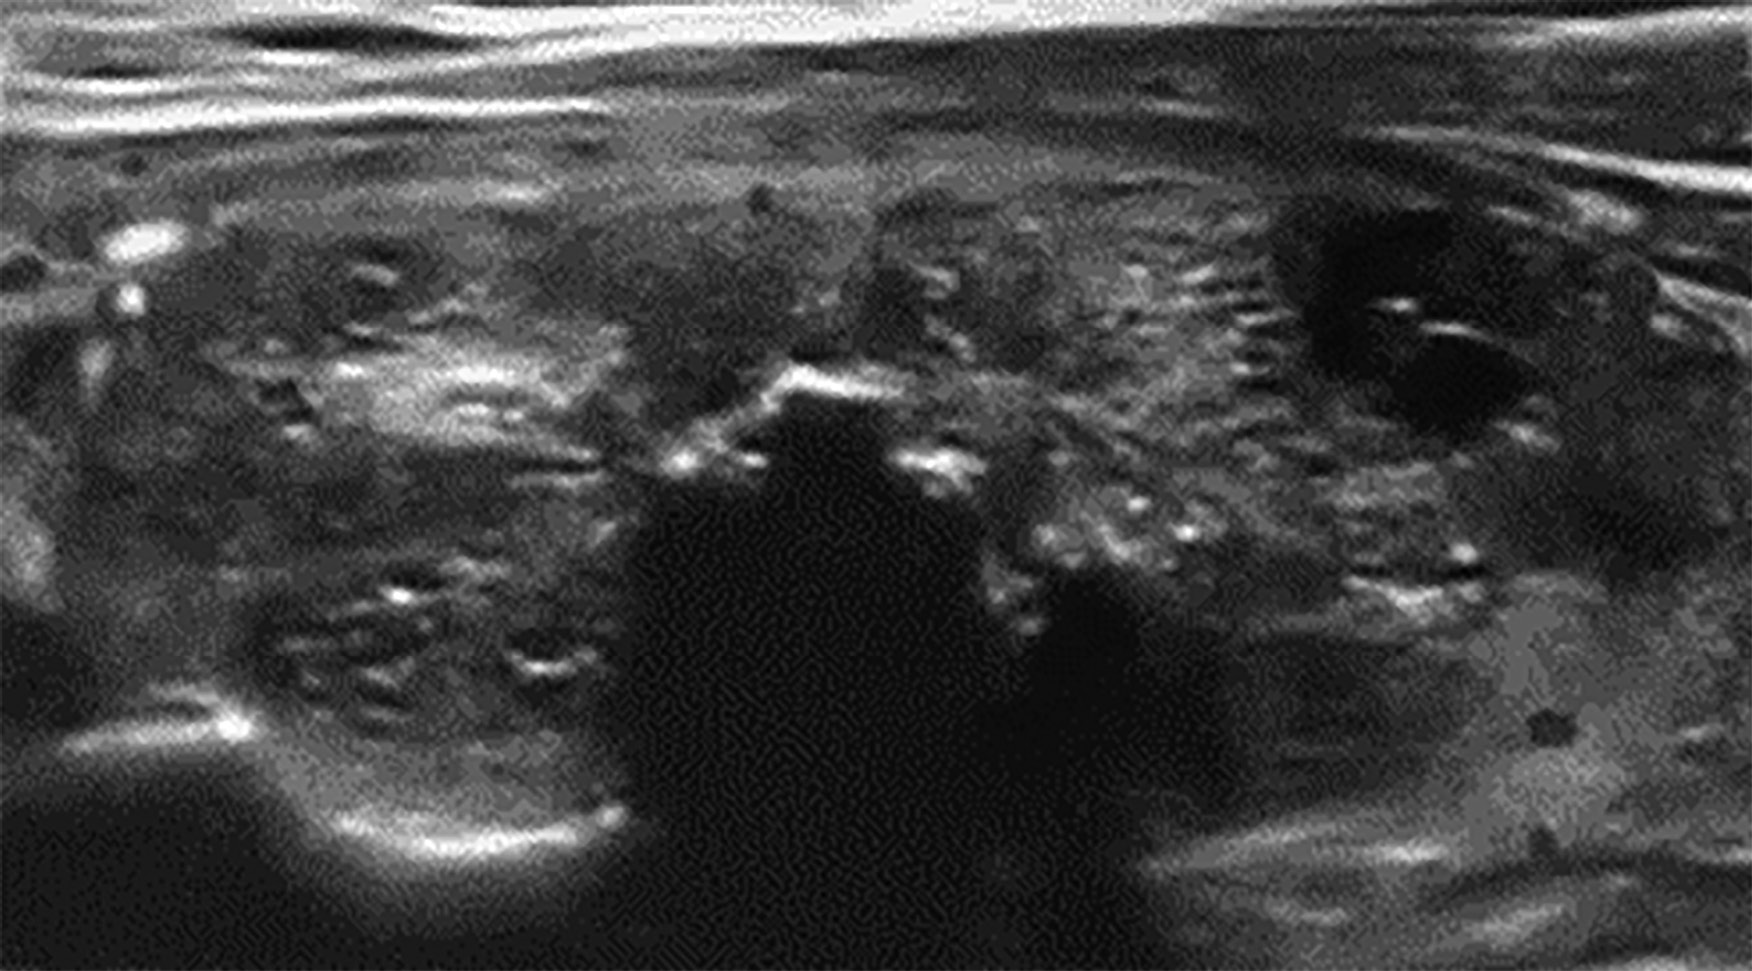

3. Рисунок 3. Результат склерозирования узла правой доли щитовидной железы.

Тема

Тип Исследовательские инструменты

Посмотреть (259KB)